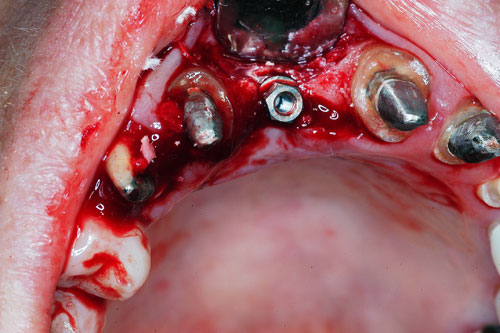

Mientras dichos movimientos ortopédicos se producen (período que supondrá otros seis meses), estudiamos los actos quirúrgicos a realizar en los cuatro implantes que pondremos. De acuerdo al estudio Desatascan realizado observamos tres situaciones diferentes: 1º-El Primer Molar Inferior Izquierdo, lo instalamos mediante Cirugía Minimamente Invasiva , con la aplicación de una Férula Quirúrgica Obtenida de los datos del scanner tratados con un programa de CMI (Cirugía Minimamente Invasiva), previa prueba en un modelo estereolitográfico, ya que la altura ósea era apenas de 9 mm. 2º- El Primer Molar Superior Derecho, se implantará mediante una ligera Elevación Atraumática (Trans alveolar) de Seno una vez logrado el espacio mesio distal necesario. 3º- El Incisivo Central Superior Derecho ausente, cuenta con un sustrato óseo prácticamente inexistente. El espesor de la tabla era de menos de 2 mm. Los caminos posibles a seguir para contar con una Rehabilitación de piezas independientes son dos: Optamos por esta segunda opción por ser menos cruenta y no necesitar de una zona dadora. Técnica esta que pondremos en práctica en dos etapas diferidas: 1º-Incisión horizontal palatinizada, incisiones peri rodetes gingivales e incisiones de descarga. Dilatación que comenzamos con dos incisiones de descarga sobre la cortical vestibular realizadas con disco. y el comienzo de la dilatación propiamente dicha mediante una hoja de bisturí, para luego seguir con un periostótomo . Recién después de alcanzada una cierta separación de la cortical vestibular de la palatina, empezamos con los dilatadores roscados. En este punto podríamos haber utilizado sin riesgos un Implante de 3,8 mm de diámetro, pero a fin de mejorar la estética del pilar emergente decidimos rellenar con material osteoconductor y osteoinductor (BiOss) y cubrir mediante membrana reabsorvible ( Bio Guide). 2º-Implantación seis meses después. Mientras se van cumpliendo los tiempos antes mencionados, y comprobamos reiteradamente la funcionalidad de la oclusión con los provisorios, tomamos impresiones definitivas y construimos primero el maxilar inferior, para definir en primer término la porción inferior de la Guía Anterior., y a nivel posterior Curvas y Microplanos. Para luego realizar los cuadrantes premolar- molar del superior: La espera de la regeneración ósea y sus tiempos pertinentes, más la espera de los tiempos de la implantación, nos obligaron a modificar las etapas del protocolo D.AT.O de manera de mantener la –D- mediante el sector superior de la GA. en provisorios, mientras fuimos resolviendo en forma definitiva los demás sectores. Ya pasados los meses necesarios para recrear un hueso adecuado en el área del Incisivo Superior Derecho, procedemos a resolver la implantación de dicha zona, observando que todo el esfuerzo dedicado al mismo había sido inútil, ya que la formación de hueso se produjo minimamente. Cuatro meses después tomamos impresiones del sector Antero Superior de la Guía Anterior, incluyendo el arrastre de un transfer . Seguimos modelando la encía con un nuevo juego de provisorios. Y se construye entonces el sector superior de la Guía Anterior. Se efectúa un control radiográfico a los 6 meses. Se ha intentado mostrar en esta Rehabilitación, que a pesar de las distintas circunstancias de cada paciente, siempre debemos tener en cuenta la necesidad de ejercer la DESOCLUSIÓN del caso como prioridad número uno, para luego perseguir la ALINEACIÓN TRIDIMENSIONAL de las arcadas y obtener así una OCLUSIÓN equilibrada. D.AT.O. ES EL PROTOCOLO QUE DEBEMOS SEGUIR EN TODA REHABILITACIÓN. BIBLIOGRAFÍA 1)William Mc Horris,B.S.,D.D.S. Oclusión. Con especial énfasis sobre :El rol funcional y parafuncional de los dientes anteriores. 2)Von Spee , Craff(Anatomista alemán, describió la curva de compensación de la articulación de molares y premolares).CURVA DE SPEE 1.89 3)Stuart,D.”Some aspects of the inervation teeth.”Procedings of Royal Society of Medicine.20:1675,19274)Muhleman,H. y Savdir,S”Tooth movility-its causes and significance”Journal of Periodontology ,36:153,Marzo ,Abril,1965. 4)Muhleman,H. Y Savdir,S”Toothmovility its causes and significance” Journal of Periodontology,36:153,marzo,abril,1965. 5-Oclusión y Diagnóstico en Rehabilitación Oral. 6-Anatomia Odontológica. 7-A contribution to the study of the movementes of the mandible. 8-Celenza F.W, Nadeskin J.F.,Oclusión.Situación actual. 9-D´Amico 10-Dawson P.E. 11-Huffman –Regenos. 12-Hobo S.-Takayama H.A. 13-Lucia V.O 14-Mc Horris. 15-Mc Horris. 16-Stuart C. 17-Vartan Veshnilian 18-Alvarez Cantoni H. AUTOR:Ratificación del Protocolo en Rehabilitación Bucal a pesar de las incidencias propias de cada caso clínico. A propósito de un caso.

Cubrimos con membrana reabsorvible.

No obstante pudimos implantar satisfactoriamente mediante un implante de 4.2 mm. de ancho y 14 mm. de largo, con una nueva R.O.G.

El implante se encontraba perfectamente según comprobaciones radiográficas y clínicas al sondeo.